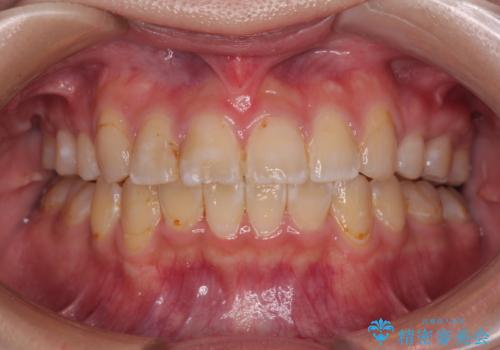

[マウスピース矯正] がたがたの歯並びをきれいにしたい

![[マウスピース矯正] がたがたの歯並びをきれいにしたいの症例 治療後](https://seimitsushinbi.jp/wp/wp-content/uploads/2025/06/IMG_0002-2-500x350.jpg?v=1750323305)